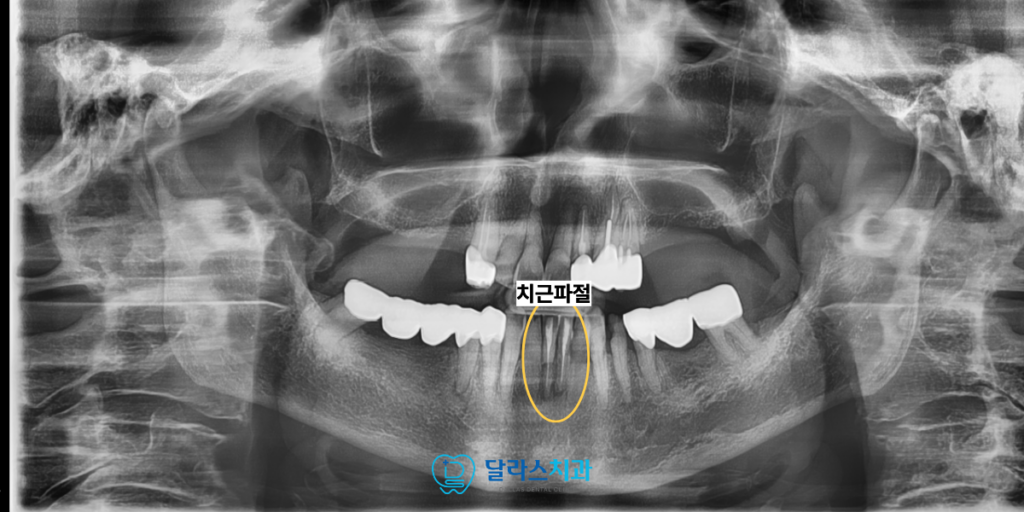

노원치과를 방문해주신 80대 여성 환자분께서는

과거에 아래 앞니 두 개에 대하여 신경 치료를 받으셨으며

위쪽 치아는 이미 전체 틀니를 오랫동안 사용하고 계셨습니다.

지속적으로 아래 앞니 부위의 불편함을 호소하며 내원하셨는데

정밀 검사 결과, 이전에 신경 치료받았던 치아의

뿌리 부분이 파절된 상태임이 확인되었습니다.

치료 전 2025.07.25

치아 뿌리에 금이 가거나 부러지는 파절 현상은

극심한 통증과 함께 주변 조직의 염증을 동반하게 됩니다.